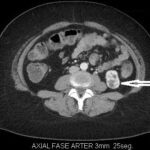

Fase corticomedular y arterial

Esta primera fase ocurre en los primeros 25 a 70 segundos posteriores a la inyección del medio de contraste; la corteza renal, al retener el medio de contraste en este tiempo en los capilares corticales aumenta de una manera intensa diferenciándose de la médula renal, que se encuentra hipodensa.

La fase arterial o corticomedular es esencial para la estadificación, extensión y planificación quirúrgica, si fuese el caso de la neoplasia encontrada, ya que ofrece un mejor detalle vascular (opacificación de los vasos), una mayor definición anatómica y de lesiones vascularizadas en el hígado, el bazo o el páncreas, consideradas dentro del contexto de una metástasis (Fig. 2).

Los errores diagnósticos que pueden presentarse durante esta fase se asocian a lesiones de pequeño tamaño; en el caso de un tumor hipervascularizado pequeño aumentaría su atenuación en la misma medida en que lo haría la corteza. Otro error que puede ocurrir es con los tumores pequeños que se localizan hacia la médula, ya que por su ubicación se mantendrían hipodensos durante esta fase 3-4.